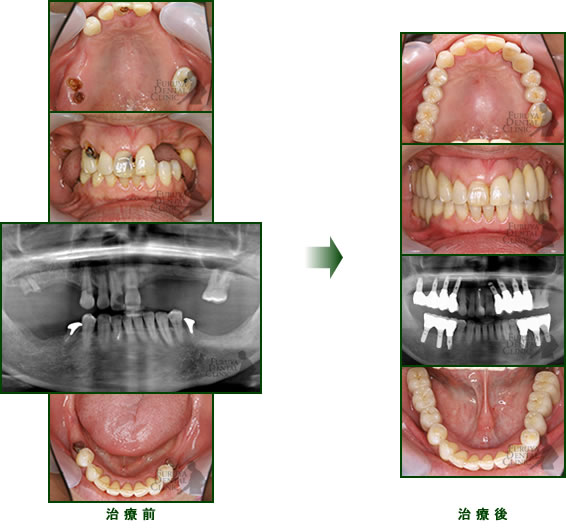

60代 女性

不適合な義歯を長期に使用していたため、かみ合わせが崩壊し、歯周病、虫歯も重度に進行していました。

時間をかけて虫歯、歯周病を手術段階まで治療、かみ合わせの再構築にインプラントを部分に分けて施術しました。

審美的にも20代の自身の口腔内以上に抗年齢を再現できたと思います。